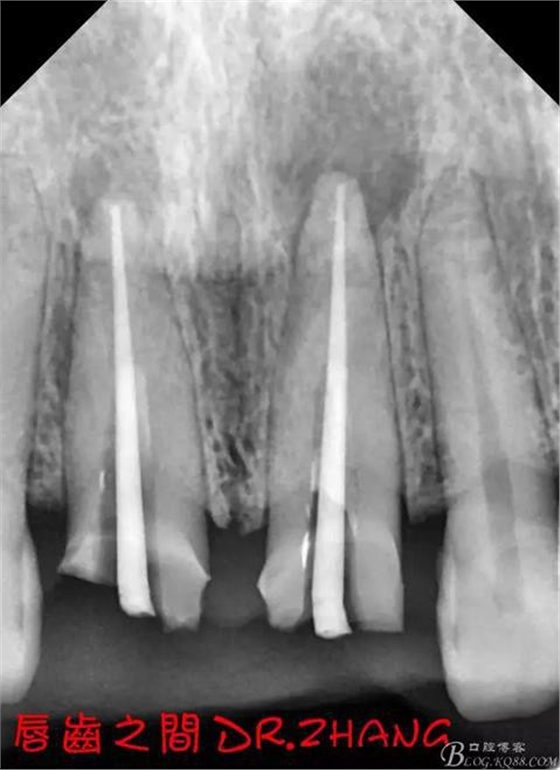

復(fù)診:腫脹明顯消失 患者自訴感覺良好 溝通后決定拆除11 21兩顆烤瓷冠后重新修復(fù) 去冠器直接去冠 去除11根管內(nèi)的充填物 15#K銼疏通根管 11 21根長均為16MM平斷面 薩尼S3系統(tǒng)機擴至2S 期間不斷用氯己定和鹽水交替沖洗 吸潮紙尖干燥根管后06 25#試尖

思博安熱牙膠系統(tǒng)根充 燙斷至根尖三分之一處后纖維樁恢復(fù)牙體組織